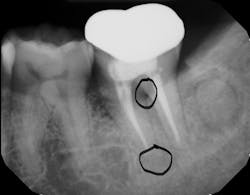

Root fracture is a common source of pain after root canal treatment and is of particular concern since it may be hard to diagnose (figure 1).5 Although new technologies such as three-dimensional imaging and microscopes have increased diagnostic ability, vertical fractures can still be hard to ascertain. Isolated periodontal pockets and a history of sharp pain that progresses to a dull throbbing pain upon mastication/palpation are common signs of fracture. Other common risk factors for fracture include: the lower second molar (most likely tooth to fracture), parafunctional habits including clenching/bruxism, large amalgam restorations, thermal injury, psychological stress, teeth with existing erosion, abrasion, and/or abfraction. A fractured tooth may need to be extracted to alleviate symptoms of pain (figure 2).